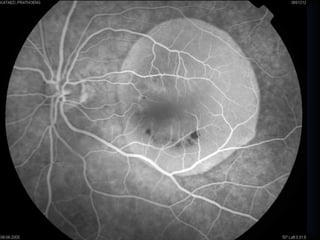

Opacities of therefractive media an of the vitreous Preretinal and intraretinal gliosis and Preretinal Retinitis Myelinated nerve fibers Intra-und preretinal hemorrhages Melanocytoma Hemorrhage ypofluoresPigment ence Intraretinal Hard exudates eakage Edema Hemorrhage Pigment Subretinal Inflammation Fluid Hard exudates Flecked-retina syndrome Different deposits Vitelliform degeneration Fundus albipunctatus